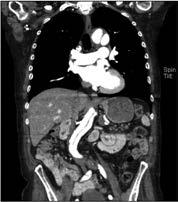

CT-Angiographie (CTA): Die CTA ist eine Untersuchungstechnik mit hoher räumlicher, aber begrenzter zeitlicher Auflösung. Auch wenn eine Applikation von i.d.R. Jod-haltigem Kontrastmittel (KM) notwendig ist und eine gewisse Strahlenexposition vorliegt, bietet die CTA die Möglichkeit der gleichzeitigen Erfassung von Verkalkungen des Gefäßes, der Beurteilung der Wandstruktur und der genauen Bestimmung der Lumenweite.

Kardiale Bildgebung

Kardio-CT: Auch im Bereich der kardialen Gefäßdarstellung ist nach wie vor die invasive Koronarangiographie in der Diagnose der koronaren Herzkrankheit der aktuelle Goldstandard. Jedoch hat die koronare CTA aufgrund ihrer hohen zeitlichen und räumlichen Auflösung einen wachsenden Stellenwert bezüglich der Diagnostik einer bestehenden koronaren Herzerkrankung, aber auch hinsichtlich eines sicheren Ausschlusses einer bestehenden revaskularisationsbedürftigen Stenose. Zudem vermeidet die CTA die mit einem invasiven Verfahren verbundenen Risiken und bietet darüber hinaus eine schnellere und möglicherweise kostengünstigere Möglichkeit zur Beurteilung von Patienten mit mittlerem Risiko für eine koronare Herzerkrankung. Die nichtinvasive anatomische Visualisierung mittels koronarer CTA ermöglicht eine direkte Darstellung des Ausmaßes und der Lage von Koronararteriosklerose und Koronarstenosen (Abb. 4).

CT-Angiographie: Die CTA ist in der Regel das bildgebende Verfahren der Wahl, wenn der dringliche Verdacht auf eine akute Aortendissektion besteht (Abb. 5b). Sie ist mit einer Sensitivität und Spezifität von nahezu 100 % sehr genau. Zudem ist sie in den meisten medizinischen Einrichtungen

Abbildung 4: Mittels CT-Angiographie des Herzens nachgewiesene Stenose des Ramus interventricularis anterior (Pfeil).

Abb. 5a Abb. 5b

Abbildung 5a, b: Darstellung der Aorta.

a: Mit MR-Angiographie erhobene Übersicht.

b: CTA-Darstellung einer langstreckigen Aortendissektion Typ A.